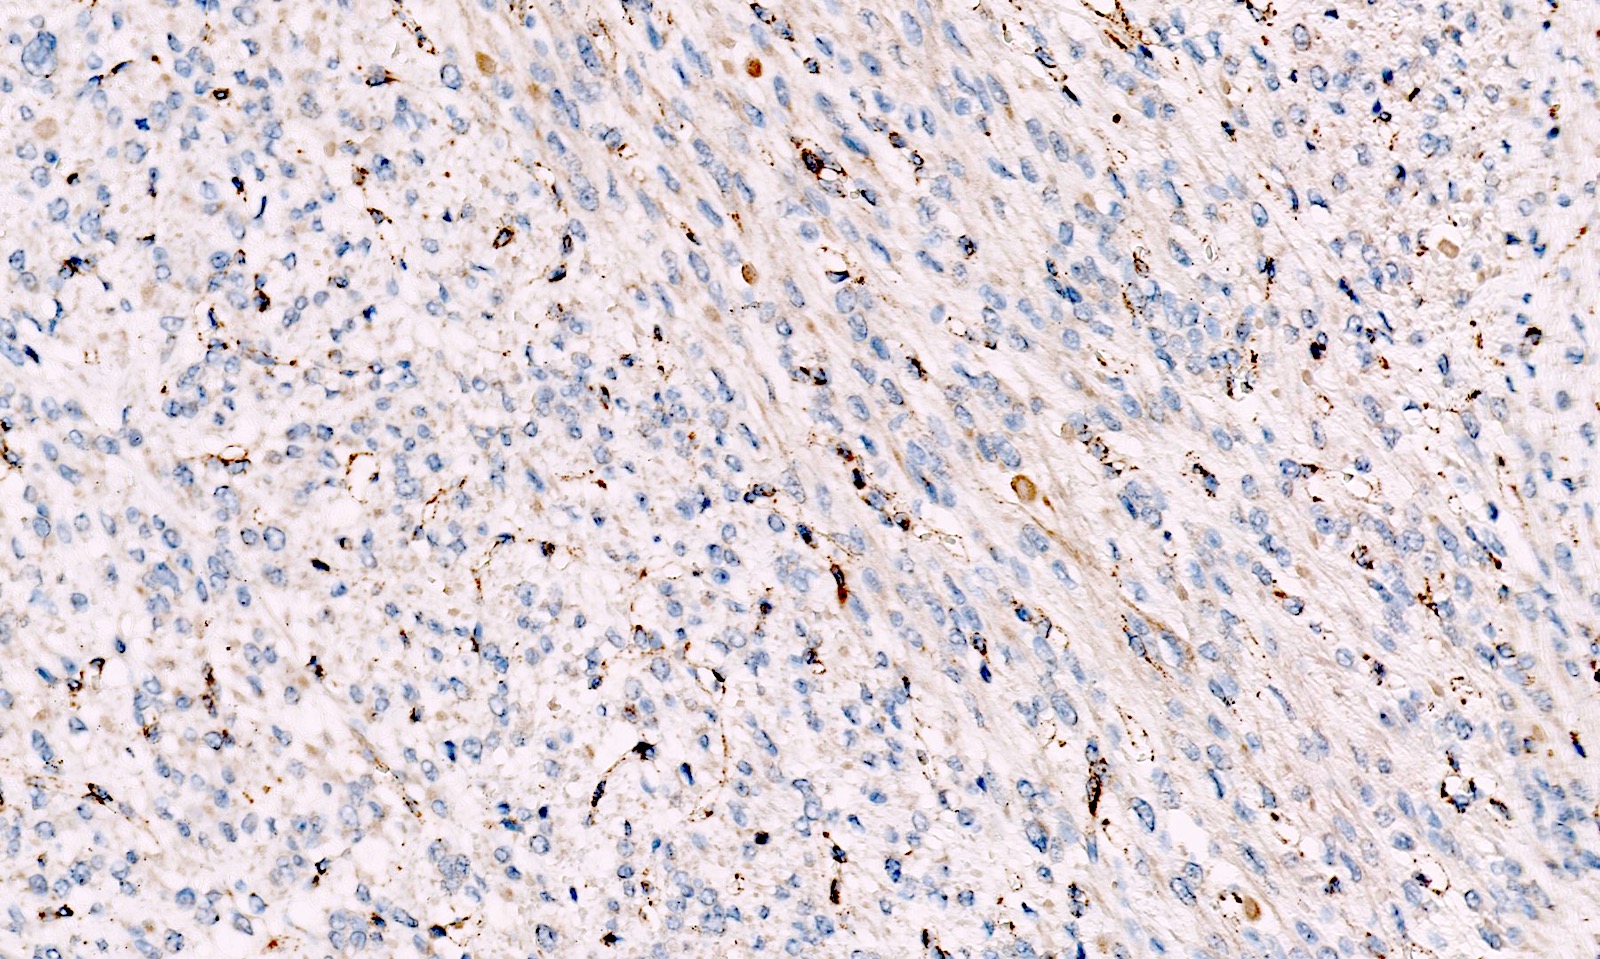

Microscopic (histologic) images

Contributed by Sabrina Croce, M.D., Ph.D., Kristina Doytcheva, M.D., Jennifer A. Bennett, M.D. (Case #508) and @Andrew_Fltv on Twitter

- FH loss of expression and 2SC positivity may be useful to identify fumarate hydratase deficient leiomyoma (Am J Surg Pathol 2016;40:599, Mod Pathol 2014;27:1020)

- FH loss of expression is specific of FH deficient leiomyoma but its sensitivity is low with different results across different leiomyomas of the same patient; for these reasons, the clinical value of FH staining is limited (Am J Surg Pathol 2015;39:1529, Am J Surg Pathol 2019;43:1170, Genes Chromosomes Cancer 2021;60:210)

- 2SC nuclear staining has been reported in FH deficient leiomyomas but is not widely commercially available and experience is limited (Am J Surg Pathol 2014;38:627, Am J Surg Pathol 2015;39:1529, Mod Pathol 2014;27:1020, Genes Chromosomes Cancer 2020 Oct 24 [Epub ahead of print])